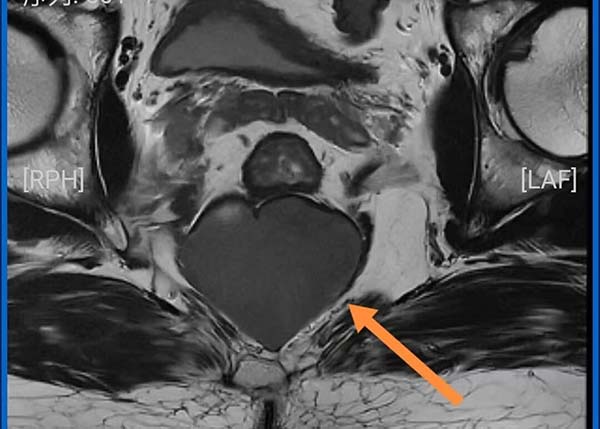

60岁的王先生5个月前行腹部CT检查时发现骶尾骨与直肠之间有一囊性肿物,但并未重视。几个月后,他逐渐出现持续性的臀部胀痛,站着疼、坐着疼、躺着也疼,更让他苦不堪言的是排便困难日益加重,最严重时可长达一周无排便。复查磁共振显示,骶前占位较前明显增大,达到5cm×5cm大小。

由于囊肿位于骶骨前方,前方和上方毗邻直肠、肛管等重要脏器,下极超过尾骨尖,若直接从肛门附近切入,虽然距离囊肿距离近,但容易造成感染甚至损伤肛门功能。北院肛肠科姜秀峰主任团队从手术安全性、彻底切除率以及术后恢复等多方面综合考量,最终决定采取尾骨旁小切口入路。这种入路既能够有效避开主要脏器与血管,减少切口污染风险,又能通过精准解剖,保证手术视野清晰。

骶前囊肿是位于骶尾骨与直肠之间的囊性或囊实性肿块,与骶尾骨筋膜、直肠及肛门括约肌等盆底组织关系密切,病理分型分为良性和恶性两大类型。